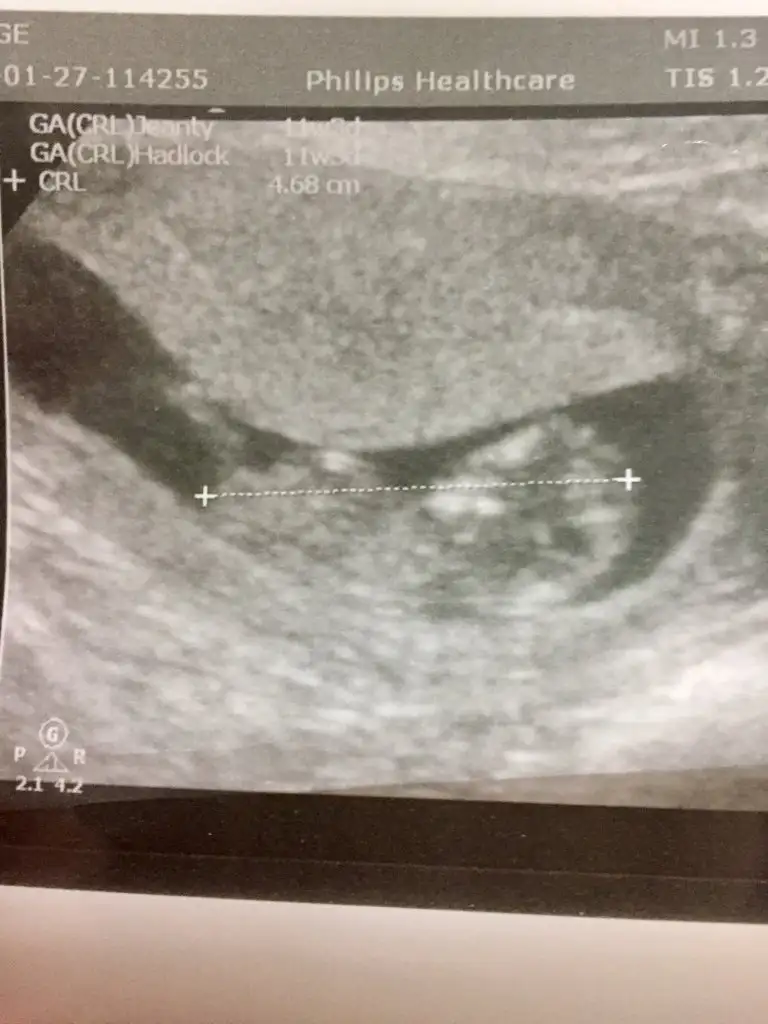

Merhaba Ikra meyra Ikra meyra rica etsem bana da bi tahmin de bulunabilir misin 🙏🏻😊11+11

• 54B101D6-D23C-441C-BC00-CC8CF32314D4.webp

54B101D6-D23C-441C-BC00-CC8CF32314D4.webp

29,7 KB · Görüntüleme: 50

• 39CF7A4C-8688-496F-8924-527F43B5EFCD.webp

39CF7A4C-8688-496F-8924-527F43B5EFCD.webp

31,3 KB · Görüntüleme: 54

• 60B99C41-D4F2-4F76-8F85-184DC7F50134.webp

60B99C41-D4F2-4F76-8F85-184DC7F50134.webp

31,8 KB · Görüntüleme: 46